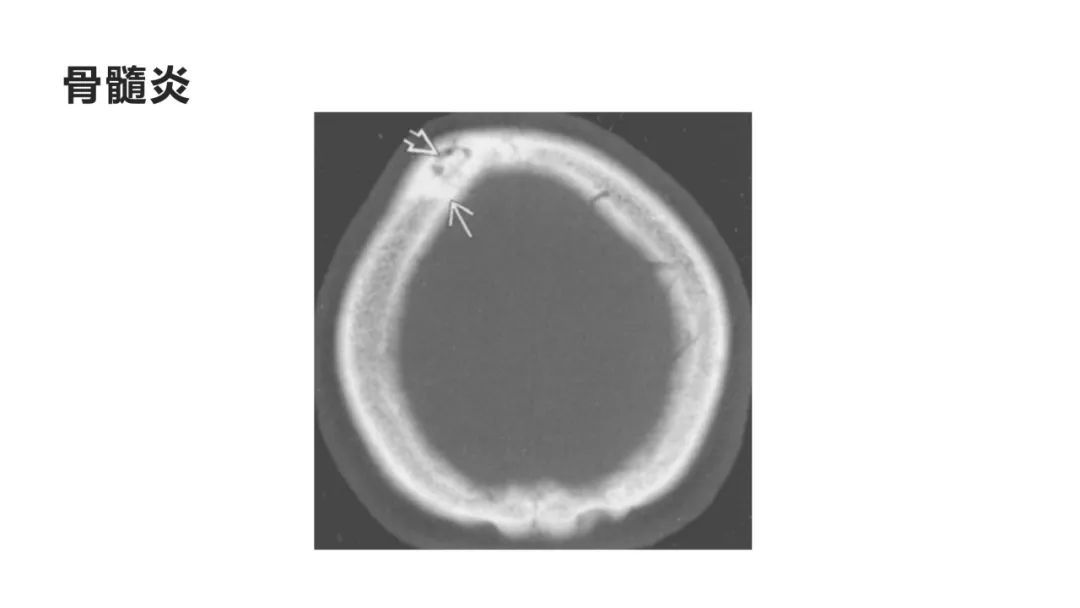

颅脑影像诊断基础知识讲座:颅骨病变